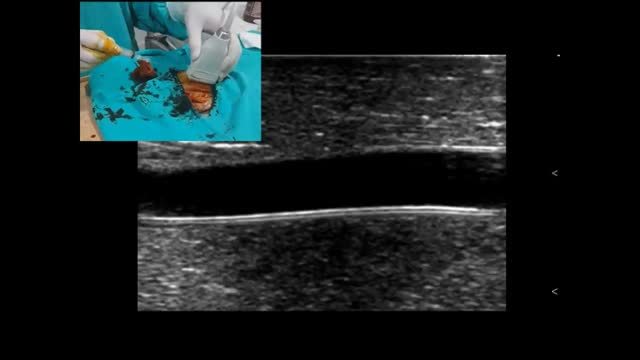

Part of this training should be accomplished in a simulated environment using “vascular phantoms”, which allow practitioners to skill the simultaneous coordination between the probe and needle manipulation as well as observing the screen, without posing any risks for the patients.21

Among other aspects, an ideal phantom should reproduce the US appearance of human tissues (also called “background echogenicity”) and vessels, replicate the texture and resistance of human soft tissues and finally have different levels of difficulty/complexity that should be easily changed.34,35 Background echogenicity is usually low in commercial phantom models, thus improving needle visibility. However, this is not the case in real practice, where human background echogenicity is higher (mixed echogenicity of muscle, fat, water) and is also combined with the echogenicity of the needle, thus causing some details to be lost. For this reason, homemade animal models, such as chicken breast based phantoms, are the best choice in the author's view to carry out realistic training in this procedure. Vessels are reproduced using modeling balloons, silicone tubes, Pezzer or Penrose catheters, all fully filled with fluids. Several phantom models can be created from superficial small peripheral veins, deep veins, small and large arteries, with practical hands-on sessions and multiple punctures for each model.34,36 In this regard, in a recent US-guided vascular cannulation study performed in a pediatric phantom model created by an avian muscular portion and modeling balloons, 866 US-guided cannulations were simulated, with 74% needle visualization and an overall success rate of 96%. Thus, it appears as a helpful training tool for physicians with varying degrees of expertise in vascular cannulations.36